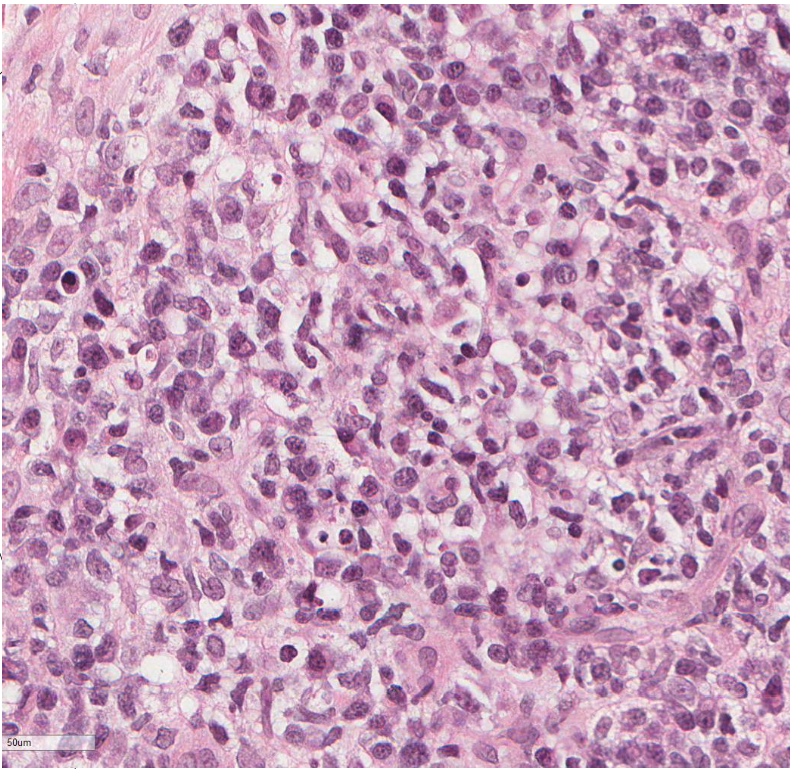

name the biological process shown in this image

acute inflammation

neutrophils !!